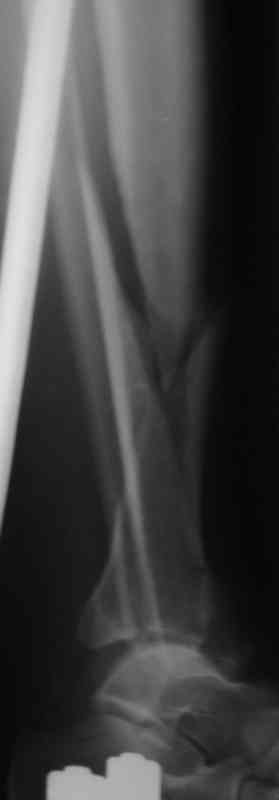

Судя по снимкам (спиральный перелом диафиза продолжающийся до сустава, отрывной перелом внутренней лодыжки) механизм перелома - скручивание. Стоит сделать снимок на всю голень включая коленный сустав и поискать проксимальный перелом м.берцовой кости. Такие переломы сопровождаются разрывом межкостной мембраны и поэтому нестабильны, повреждение м.т.

значительное и как правило большие гематомы.

Внутрисуставной перелом простой - линейный, по этому не должно быть проблем с закрытой репозицией на ЭОПе. По моему мнению самый подходящий метод -

аппарат. Важно анатомическая репозиция сустава c компрессирующей фиксацией спицами с напайкой. Если операция в отдаленные сроки - более 10 дней и закрытая репозиция не получается, стоит небольшим доступом открыть сустав и очистить перелом. Внутреннюю лодыжку лучше фиксировать открыто шурупами или по веберу.